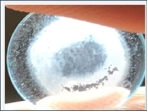

很多人曾經(jīng)有這樣的經(jīng)歷:每天明明很仔細(xì)地清洗OK鏡了,但醫(yī)生還說OK鏡沒洗干凈!看到裂隙燈下被放大的鏡片后,我們都驚呆了,看似很干凈的鏡片表面竟附著一層沉淀物。醫(yī)生為什么要反復(fù)強(qiáng)調(diào)OK鏡的除蛋白清潔護(hù)理?如何給OK鏡做高效的清潔護(hù)理?

OK鏡的鏡片表面不是只有一個(gè)基弧的球面,而是一個(gè)多弧設(shè)計(jì)的非球面,反轉(zhuǎn)弧區(qū)的設(shè)計(jì)易沉積蛋白質(zhì),且該區(qū)的凹槽處很難用手揉搓到位。